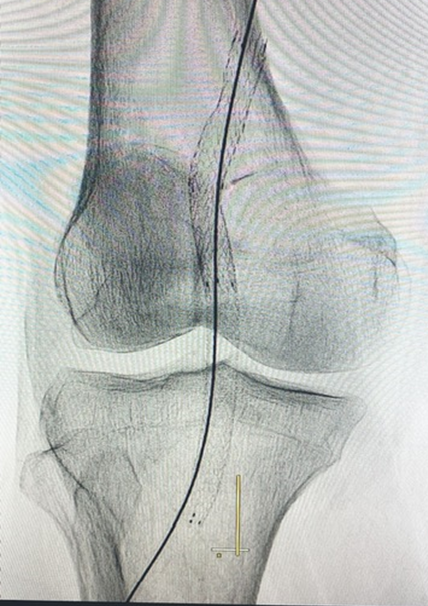

The patient was scheduled to undergo endovascular treatment of the popliteal artery aneurysm. Under general anesthesia, a right common femoral artery was antegrade punctured guided with a duplex ultrasound to perform the whole intervention percutaneously with a 6F 11cm sheat. After the puncture, the Perclose Proglideâ was inserted, in order to preload and guarantee the sealing of the puncture. Then, a 0,035”260cm Terumo â was used to perform the crossing over the distal arteries. The patient was heparinized with 5000UI intravenous in bolus. We performed a right limb arteriography to confirm the popliteal artery aneurysm (Figure 2). The popliteal artery was properly catheterized and we changed the guidewire for an Amplatz 0,035”260cm, in order to place a 11cm 11F sheat. After proper evaluation, two a covered self-expandable 8x100 and 10x75 Merit Wrapsodyâ were placed under roadmap into the distal popliteal artery and proximal femoral artery respectively, and post dilatated with a 8x100 and 10x100 catheter balloon Oceanus figures 3 and 4. There were no endoleaks, and the popliteal artery patency was identified. All the materials were removed, and we completed the final step of the perclose Proglideâ puncture closing. The patient was transferred to the nursery room, being discharged from the hospital two days after the surgery with no complications, femoral, popliteal and podal pulses present bilaterally, taking Rivaroxaban 20mg / day and Clopidogrel 75mg/day. After 1 month the patient was evaluated, presenting no further symptoms, no palpable mass in the right popliteal artery, and was submitted to a Duplex Ultrasound (Figure 5), that showed deep popliteal artery patency, stent patency, reduction of the aneurysm sac and no endoleaks. Furthermore, after one year follow-up, the patient remained asymptomatic, with Duplex Ultrasound showing popliteal artery with stent patency and no endoleaks. (Figure 6).

Figure 3: Post-operative arteriography showing covered self-expandable 8x100 and 10x75 Wrapsodyâ into the popliteal artery.

Figure 4: Post-operative arteriography showing covered self-expandable 8x100 and 10x75 Wrapsodyâ into the popliteal artery.